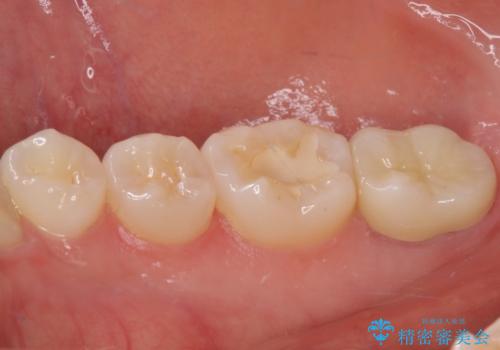

歯の高さが低く、かぶせものを安定して維持させることができないため、歯冠長延長術により歯の高さを増大させた上で、オールセラミッククラウンにて補綴することとしました。

歯の高さが増したことで、かぶせものが外れにくくなったことはもちろん、今まで無理と言われていたセラミッククラウンも装着でき、さらには歯間部の清掃性も向上したため、患者様には大変満足していただけました。